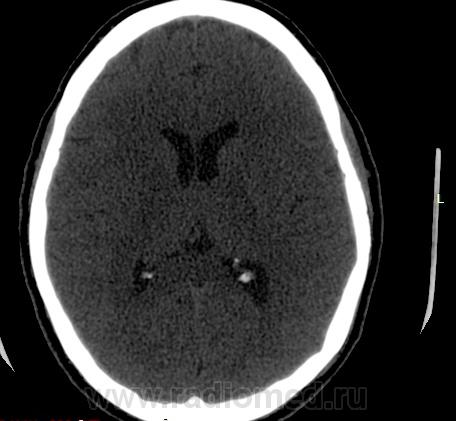

Прошу разрешить спор. По КТ - норма. Женщина, 1967г.р., жалобы на головную боль, больше в затылочной области. По-моему, не КТ-шное это дело но всеж...

Открыл. В мозгу ничего осбенного не увидел. По поводу Киари ничего не скажу, на аксиалах не вижу, а реконструкции эти срезы не строят Да и отношусь я к этой патологиии как к норме.

Но мне показалось, что всеж, для 1967г.р., не очень норма, придираюсь уже, пора на покой .

Аномалию Арнольда-Киари 1типа.

На МРТ выставили  аномалию Арнольда-Киари 1, нам сказали фу... На что я ответил, что по " ловцу и рыба". Во - первых, линию на КТ провести сложно ( в данном иссл.), во-вторых - естественные артефакты костей основания. И вообще пошли на...МРТ! Но осадок остался.